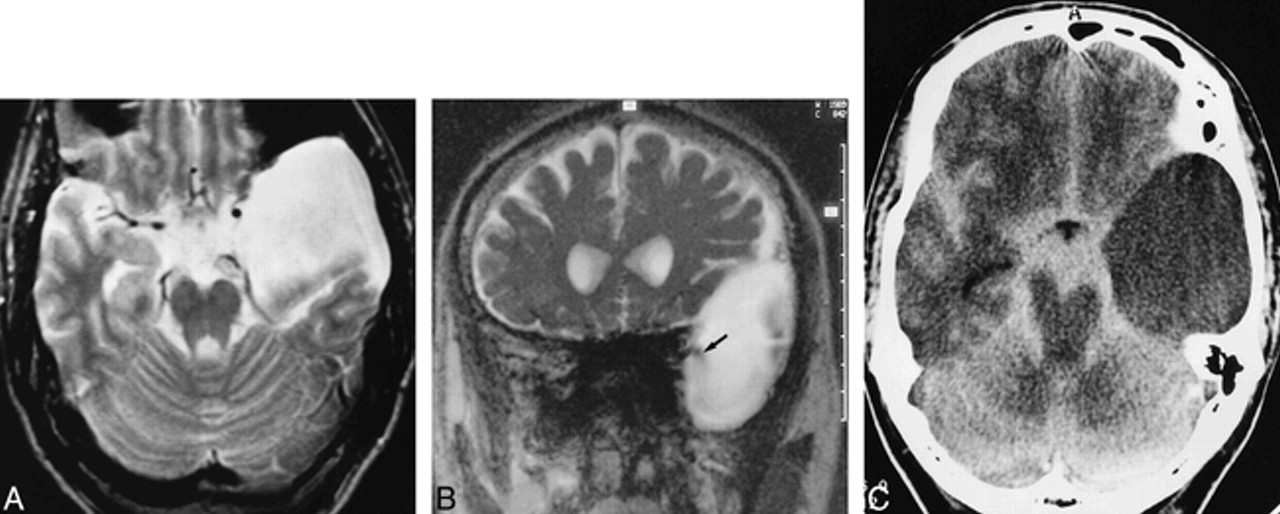

28-year-old man with a prepontine arachnoid cyst, corpus callosum anomaly, hydrocephalus, ventriculoperitoneal shunt, and headaches.

A, T2-weighted axial image (2000/80/1) shows a hyperintense cyst (arrow) within the prepontine cistern, pushing the crura cerebri and the optic chiasm apart.

B, Midsagittal T2-weighted section (2000/80/1) shows defined margins of the cyst (straight black arrows), except for the narrowing between the basilar artery and skull base (white arrow). Note callosal dysplasia (curved arrow). The bottom of the third ventricle is elevated.

C, Midsagittal SSFP image (20/25/1) reveals broad-based signal void within the cyst (black arrow) probably due to transmission of pulsations from the basilar artery. A continuous jet phenomenon between the prepontine cistern with pronounced signal void (straight white arrow) on the one hand and the cyst on the other hand is not demonstrable, making communication unlikely. Flow void within the fourth ventricle was absent (curved arrow) owing to occlusion of the aqueduct. Membranectomy was not performed, because the patient had no evidence of visual impairment.